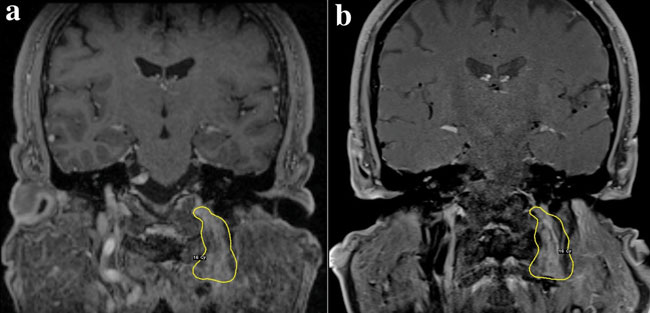

Figure 1. T1 weighted MR imaging with Gadolinium in the coronal plane, at the moment of GKS (a) and 30 months after (b), showing shrinkage of the PGL. The tumor is enclosed by the 16 Gy (50%) isodose line.

The patient underwent surveillance imaging, serology and clinical assessment at 19 and 30 months after salvage radiosurgery and remained clinically stable and without new neurologic deficits. Biochemically, the plasmatic concentration of free methoxytyramine gradually declined from 0.14 nmol/l (2*URL) before GKS to 0.07 nmol/l 30 months after GKS (1.1*URL), confirming the efficacy of the treatment (Table 1 and Figure 2). Furthermore, their urine concentration from 1803 (before GKS) was decreased to 1232 nmol/l (at 30 months after GKS), a 31.7% decline compared to pre-surgical values (Figure 2). The MR already showed shrinkage of the tumor at 19 months, which persisted over time (Figure 1b). At the last MRI, the remnant tumor volume measured 4.21 cc, which corresponded to a shrinkage of approximately 36.6% from the initial target volume (as calculated in the Leksell GammaPlan station, Elekta Instruments, AB, Sweden, the same as for the measurement of the initial GKS target volume).